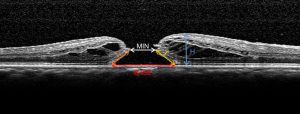

OCT examinations were performed by experienced technicians. A 20°×20° volume acquisition protocol was used to acquire a set of 25 horizontal and vertical cross-sectional B-scan images, each of which was composed of 512 A-scans. The image through the center of the IMH was determined by the simultaneous evaluation of the red-free image on the computer monitor of the OCT scanner, and only the horizontal scan showing the center of the IMH was exported for the OCT parameters measurement (16).

The preoperative macular OCT parameters [i.e., MIN, BASE, height of hole (H), temporal and nasal arm length of hole (T and N)] were manually measured by two independent retinal specialists (X.Z., Y.X.) using ImageJ software (version 1.8.0). The two retinal specialists were unaware of postoperative IMH status when the measurements were performed. The mean values of the measurements were used for training and validating the ML models (Figure 1). To measure the repeatability between the two retinal specialists, the intra-class coefficient (ICC) was calculated. MIN was defined as the minimum extent of IMH, while BASE was defined as the extent of IMH at the retinal pigment epithelium (RPE) (17,18). H was defined as the distance from RPE to the innermost aspect of the hole margins, while T and N were defined as the distances between the temporal endpoints or the nasal endpoints of MIN and BASE (16). After measuring all preoperative macular OCT parameters, four indices were calculated: HFF [defined as (T + N)/BASE], MHI (defined as H/BASE), DHI (defined as MIN/BASE), and THI (defined as H/MIN) (18-20).